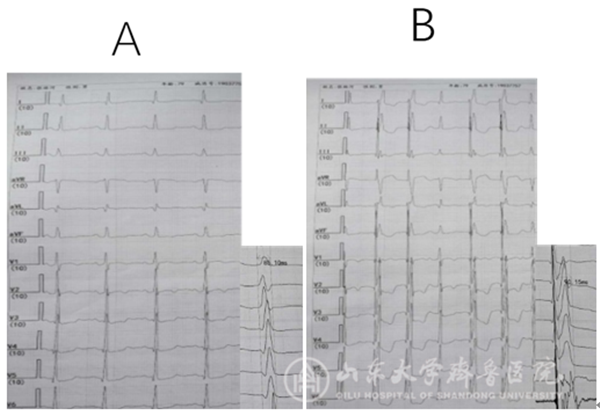

示例1:患者1为起搏器依赖不伴有心衰患者,中年女性,诊断为间歇性高度房室传导阻滞。

(心室电极置入前后心电图变化,A自身心电图,QRS间期110.10ms; B左束支区域起搏心电图,QRS间期102.53ms)

(心室电极置入前后心电图变化,A自身心电图,QRS间期85.10ms; B左束支区域起搏心电图,QRS间期90.15ms)